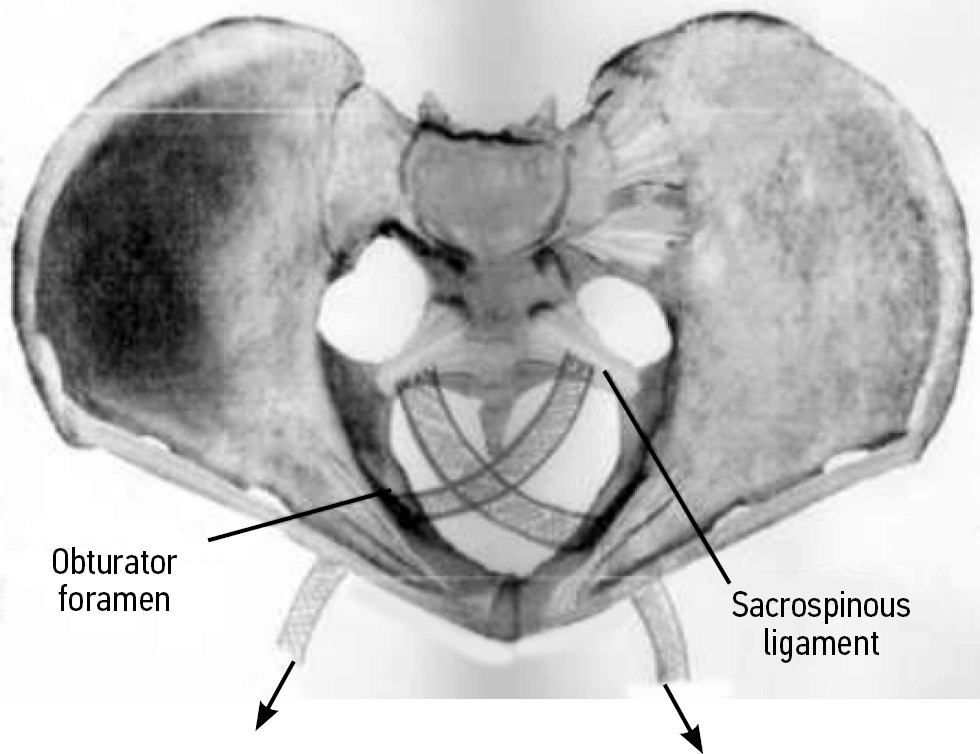

After peritonization, channels were formed toward the ischial spines and sacrospinous ligaments. Departing 1.5–2 cm from the ischial spines, a titanium fixator with a ligature was inserted into the thickness of the sacrospinous ligament. During device installation (titanium fixator), a non-absorbable fixing thread was passed through the holes in both protrusion lugs; the distal end of the bent guide was passed inside the fixator and fixed. Both ends of the thread were fixed on the handle of the guide. The conductor together with the fixator was passed into the thickness of the tissues and brought to the right sacrospinous ligament approximately 2 cm medially to the internal spine, and then it was inserted into the ligament to a depth of 1 cm. The conductor was disconnected from the fixator by rotation around its axis and removed in reverse. Pulling the ends of the ligature (ligature 1), the strength of the fixator set was checked. Similarly, the second fixator with a thread was passed and fixed in the region of the left sacrospinous ligament (ligature 2). The free ends of the threads (ligatures 1 and 2) were fixed to the sacrospinous ligaments prepared by using narrow ribbon-like mesh titanium implants alternately on both sides.

The free end of the titanium implant, fixed to the left sacrospinous ligament, was passed through the membrane and muscles of the right obturator foramen of the pelvis using a conductor under the control of the index finger, and then it was brought out into the right inguinal-femoral fold at the level of the clitoris with an incision on the skin approximately 0.7 cm (stage II). The second titanium implant was fixed to the right sacrospinous ligament and removed through the left obturator foramen.

Under visual control, the peripheral ends of titanium tape-like implants, which were brought into the region of the inguinal-femoral folds, were tightened, providing stable support for the vaginal dome. By pulling on the ends of the titanium tapes, which were brought out through the obturator membranes, the vaginal vault was fixed as high as possible in the small pelvis (stage II).

Afterward, the mesh implants were sutured with two to three slowly absorbable ligatures to the monoblock (sacral–uterine–cardinal complex), which were simultaneously sutured together (Fig.).

Fig. Fixation of mesh titanium implants to a ligamentous monoblock (sacro-utero-cardinal complex).